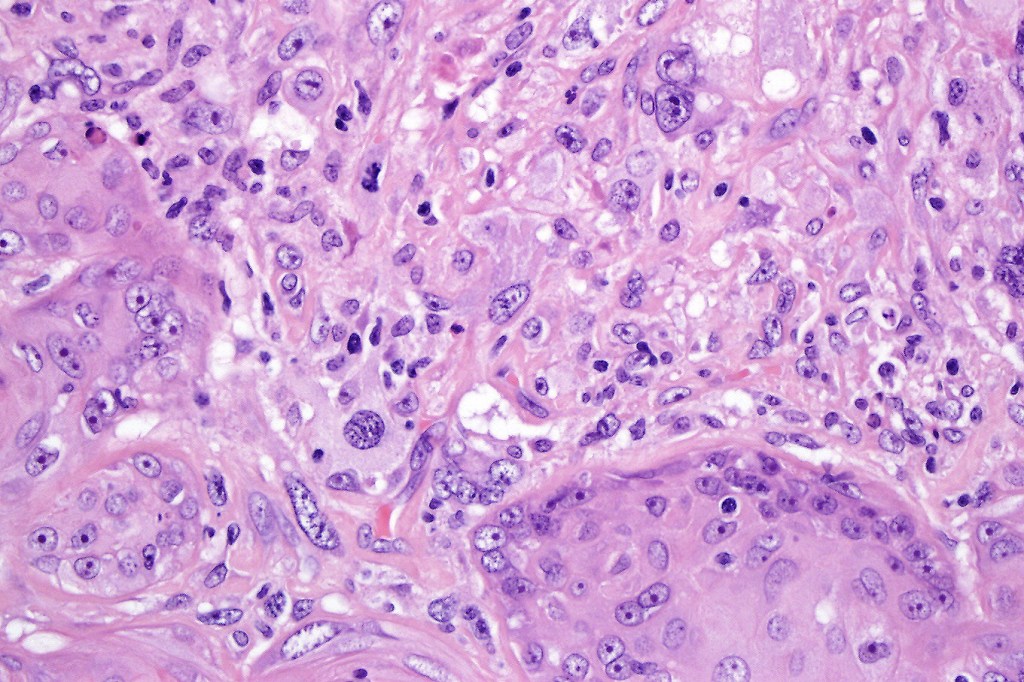

Carcinosarcoma

Cutaneous carcinosarcoma (metaplastic carcinoma, carcinoma with heterologous differentiation)

Histological features

•Osteoid

•Chondroid

•Smooth muscle

•MFH-like features with osteoclasts

•Neural differentiation